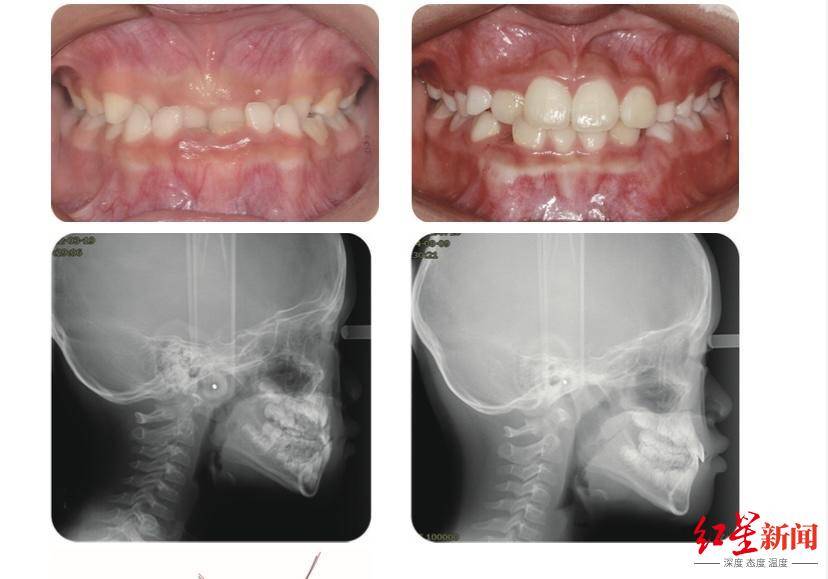

长沙牙齿矫正高难度案例埋伏牙咬合紊乱复杂治疗

6亿儿童 华西口腔医院专家:三大因素造成,早期矫治可